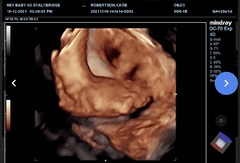

Kt1111 · 19/12/2021 21:51

29 weeks and 2 days now- she got fed up at the 4d scan and put her hand on o cover her face - I love the hbd a foot pic. ♥️ I hope you ladies get some good news soon! Xx